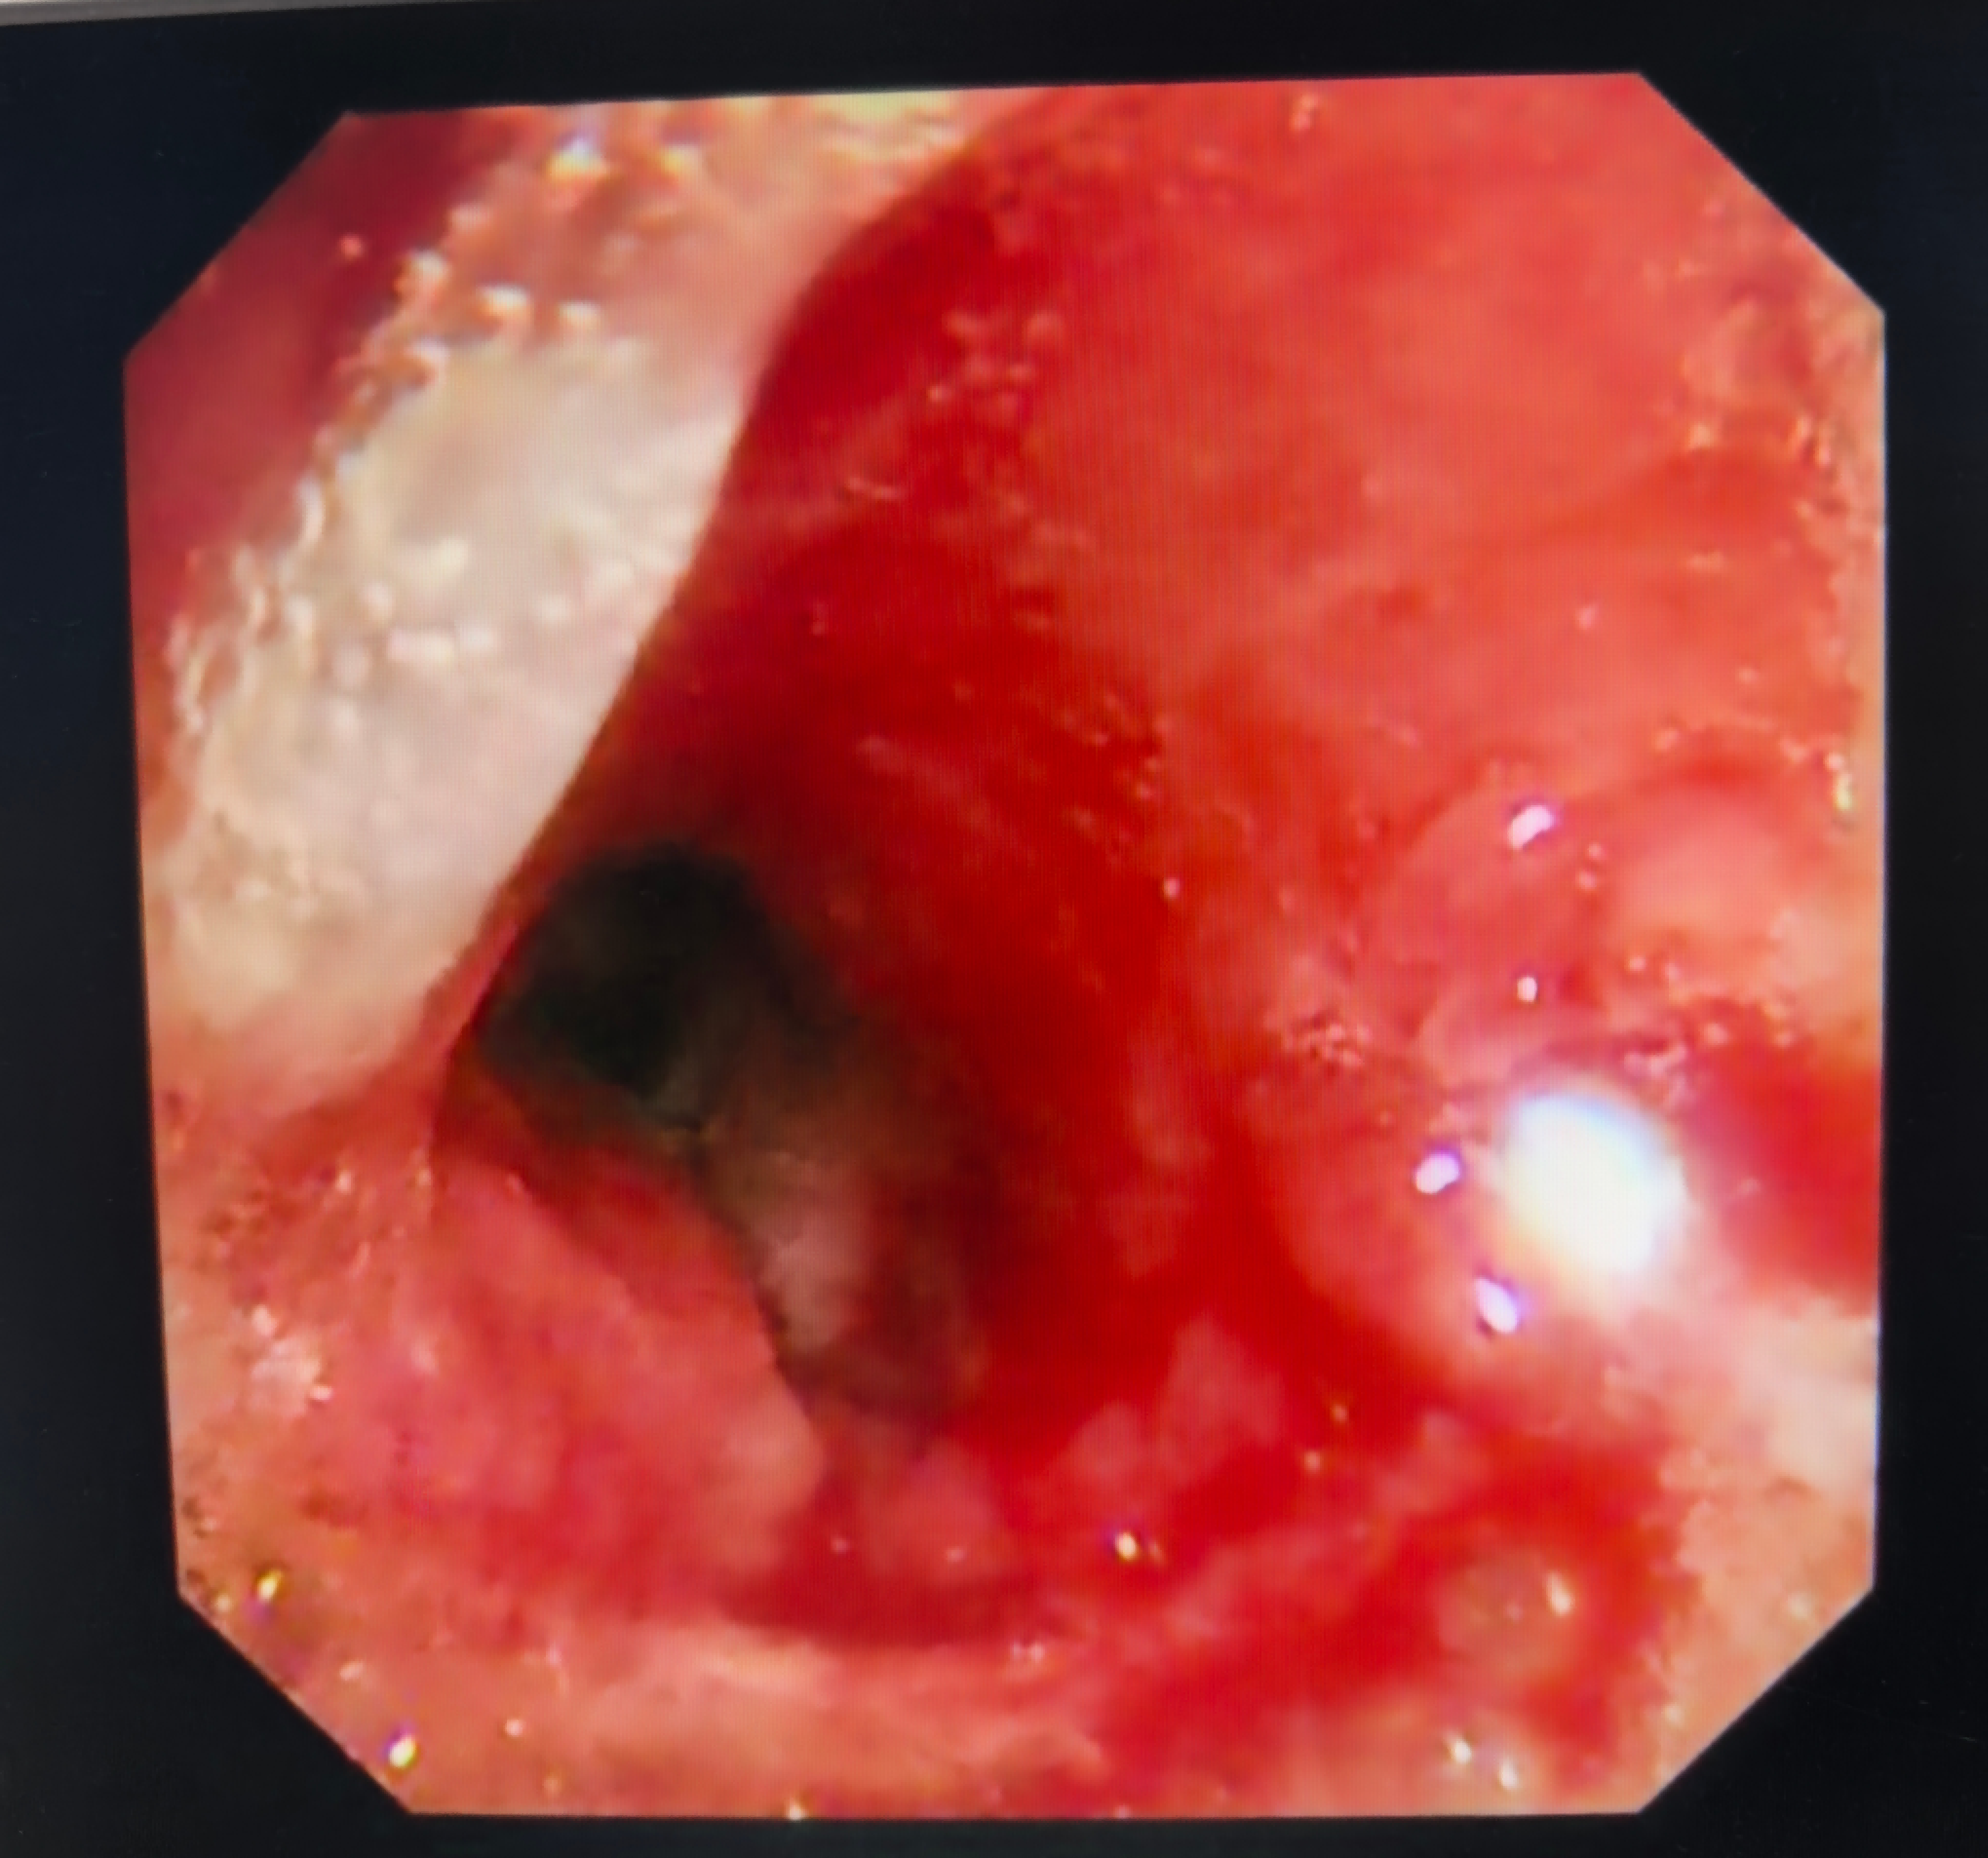

图1 床旁支气管镜可对患者气道状况进行评估

版权图片 不授权转载